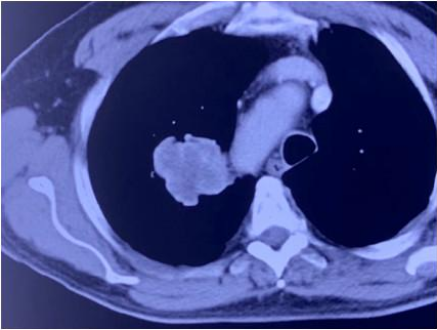

广州复大肿瘤医院牛立志教授介绍,患者原本有肾癌,手术后在肺上发现转移灶,转移灶大小达到四公分。当地的医院没有任何治疗方案,在了解到广州复大肿瘤医院的微创消融技术对肺的转移癌治疗效果比较好时,患者便来到广州复大肿瘤医院接受治疗。

牛立志教授用2.0的微波针,穿刺到肿瘤中心,十分钟就将肿瘤消融掉了。消融后,可以看到肿瘤被烧死,同时看到毛玻璃样改变。

整个过程,全程“零出血”。这证明采用微波消融是一个正确的选择。